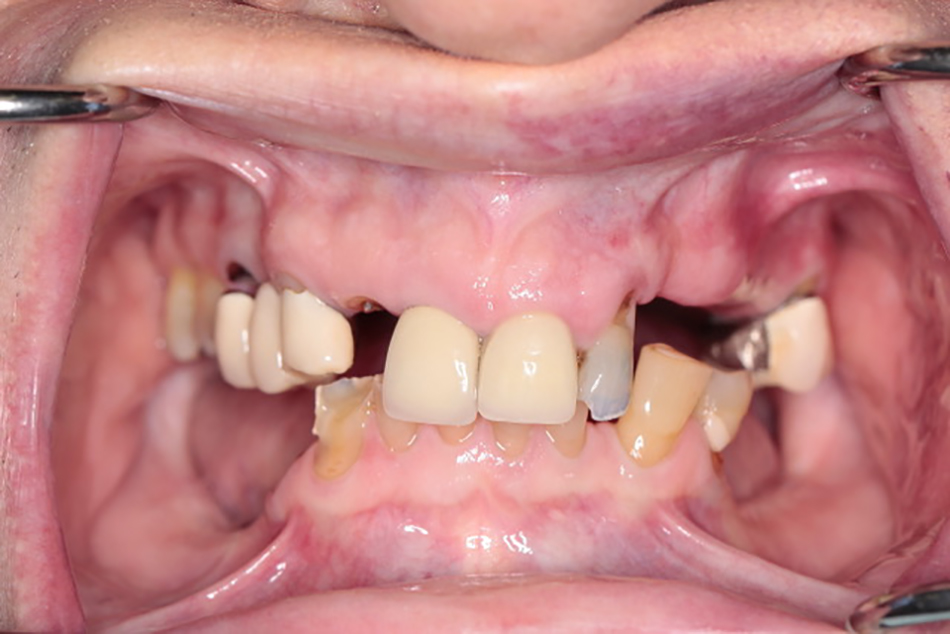

Patient 1 - Before

Patient presented with missing teeth. He was very unhappy with his smile and function.

Patient 1 - After

Patient rehabilitated with a complete denture in the upper jaw and implant supported fixed bridge on the lower jaw.